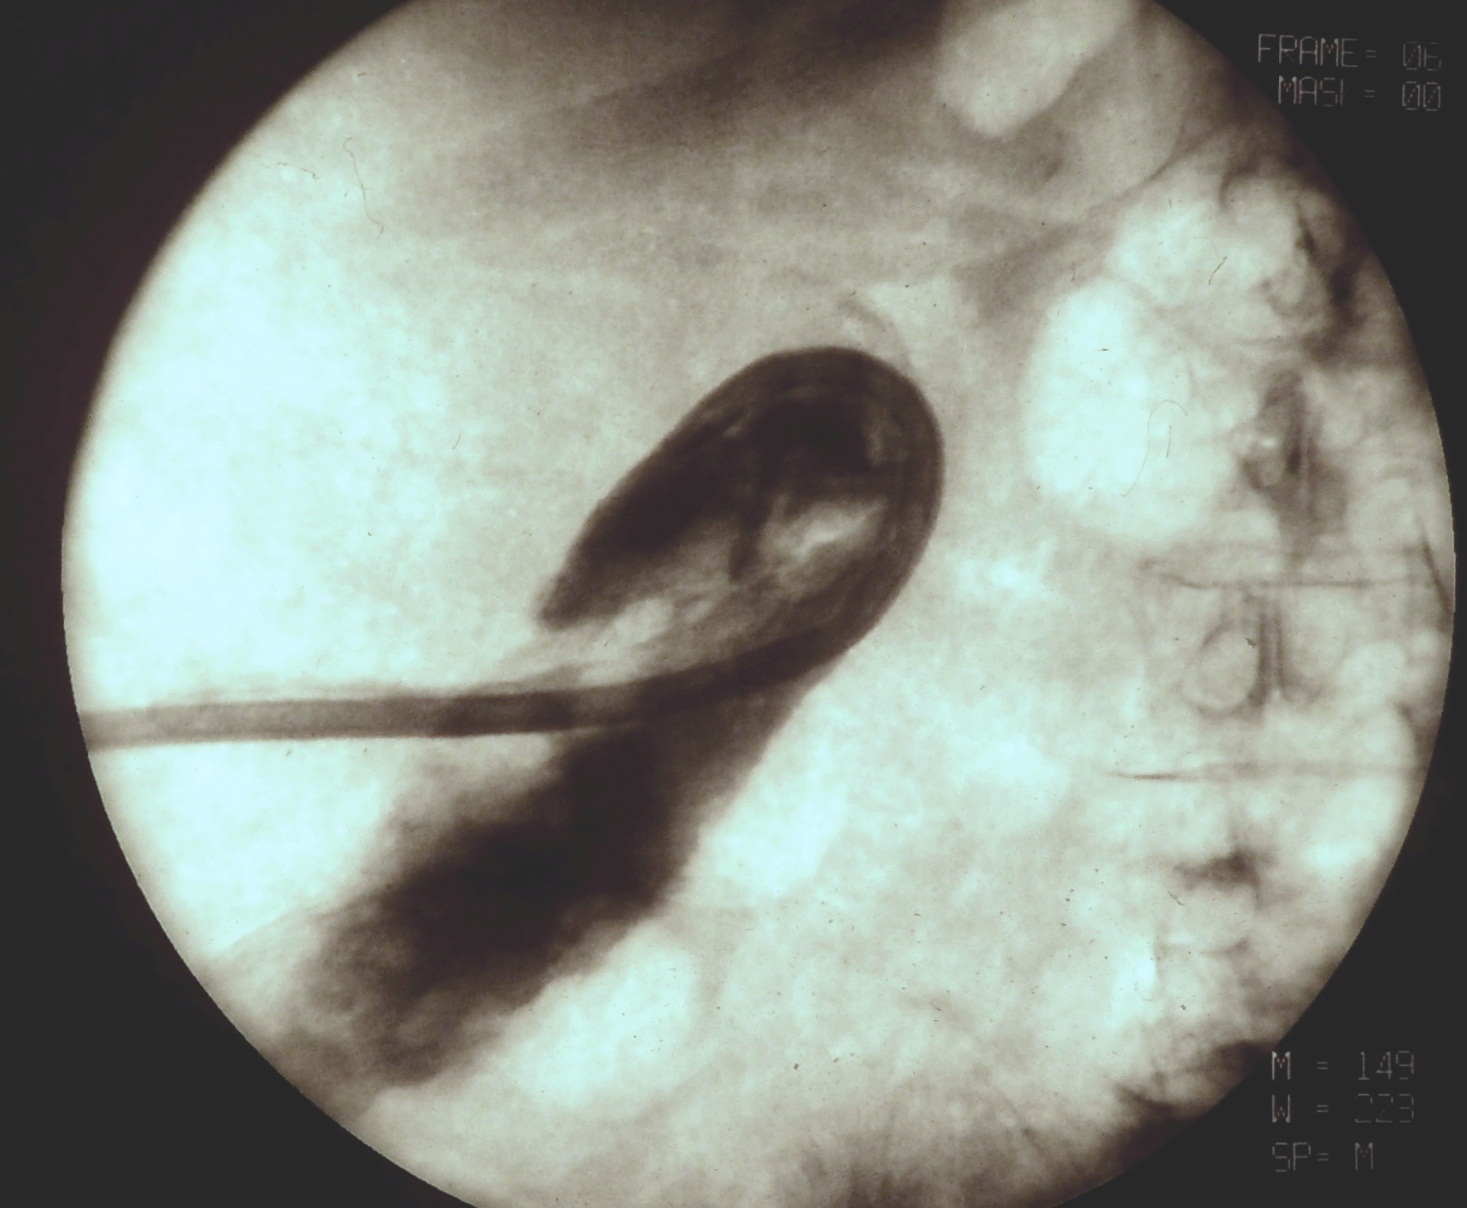

19.5.2. Percutaneous transhepatic drainage (PTD)

After a diagnostic PTC is successfully performed and a guide wire is positioned over the stenotic or occluded segment of the choledochal duct an external-internal drain (PTD) can be installed. (Figure 23.) If desired, a self expanding metallic stent could be used to override the stricture (Figure 24.)

Image

Figure 23. – PTD (Percutaneous transhepatic external-internal drainage)